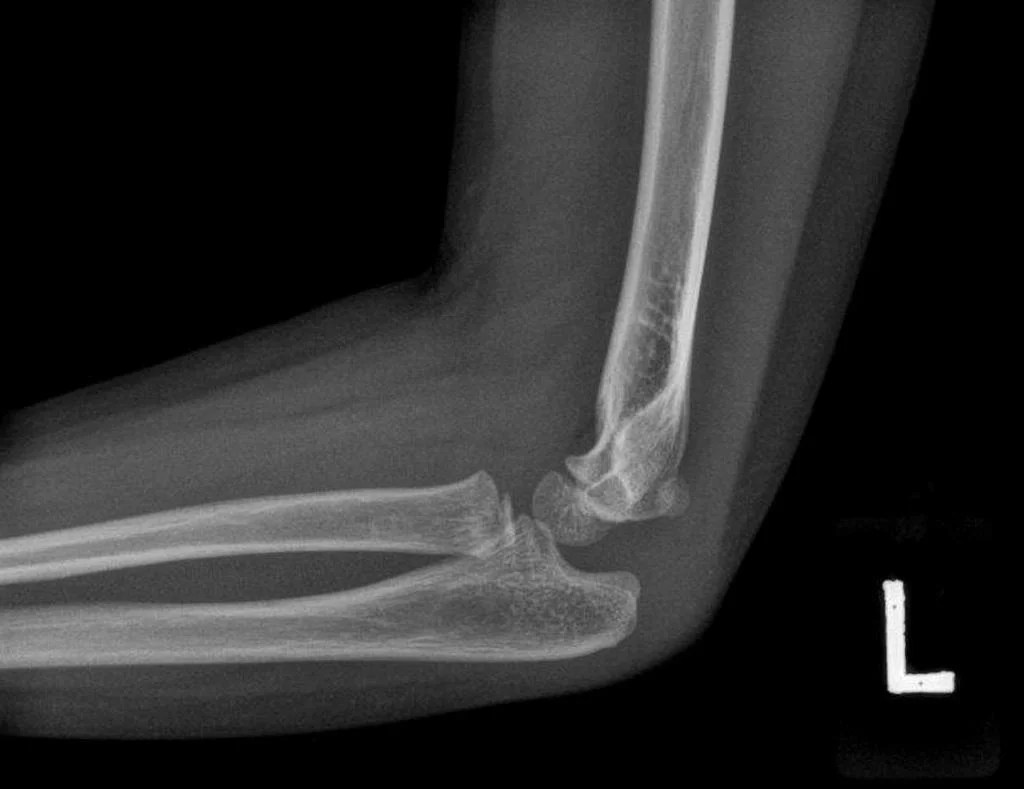

[pmc free article] [google scholar] kessler i, silberman z. The wrist anatomy comprises the distal radius and ulna, eight carpal bones, and the bases of five metacarpals. The bones comprising the wrist include the distal ends of the radius and ulna, 8 carpal bones, and the proximal portions of the 5.

The anatomy of the wrist joint is extremely complex, probably the most complex of all the joints in the body. The wrist must be extremely mobile to give our hands a full range of motion. It is formed by the distal edges of the arm bones, the radius (largest forearm bone) the ulna and the carpal bones, which are:

Wrist anatomy is the study of the bones, ligaments and other structures in the wrist. There are three joints in the wrist: However, it is susceptible to injury, especially from repetitive strain.